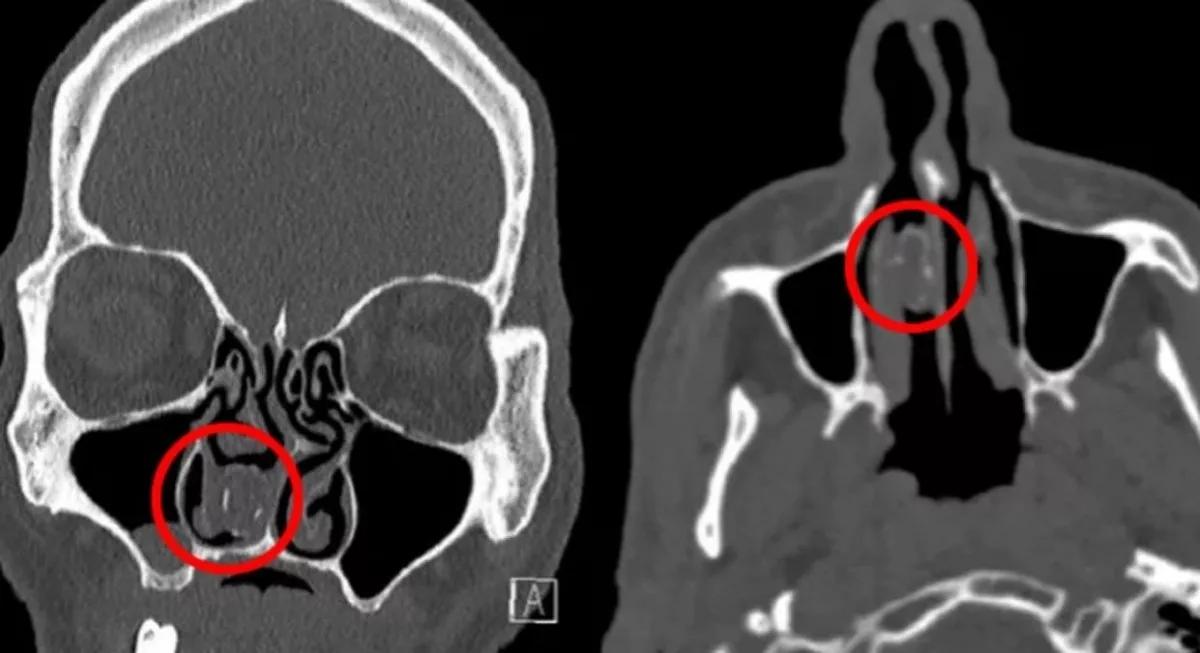

Radiografía cannabis en la nariz

También fue una sorpresa descubrir el caso de un hombre al que le extrajeron de la nariz unos restos de marihuana que tenía alojados desde hacía 18 años. El hombre acudió al médico por dolores de cabeza y un escáner del cráneo reveló un objeto en una cavidad nasal que resultó ser un globo con restos de cannabis. Según dijo el tipo 18 años atrás había estado ingresado en prisión y un día su pareja le llevó algo de marihuana en una visita a la cárcel. El hombre había introducido la marihuana en un globo y luego se lo había metido por la nariz para eludir los controles de la cárcel. Para que pasara desapercibida el hombre acabó empujando tanto el globo que pensó que había acabado por tragárselo. Pero no se lo había tragado.